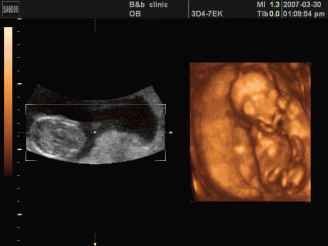

活泼的小宝宝,在妈妈肚子里手舞足蹈

颇有迈克杰克逊的影子,未来给TA学跳舞吧!